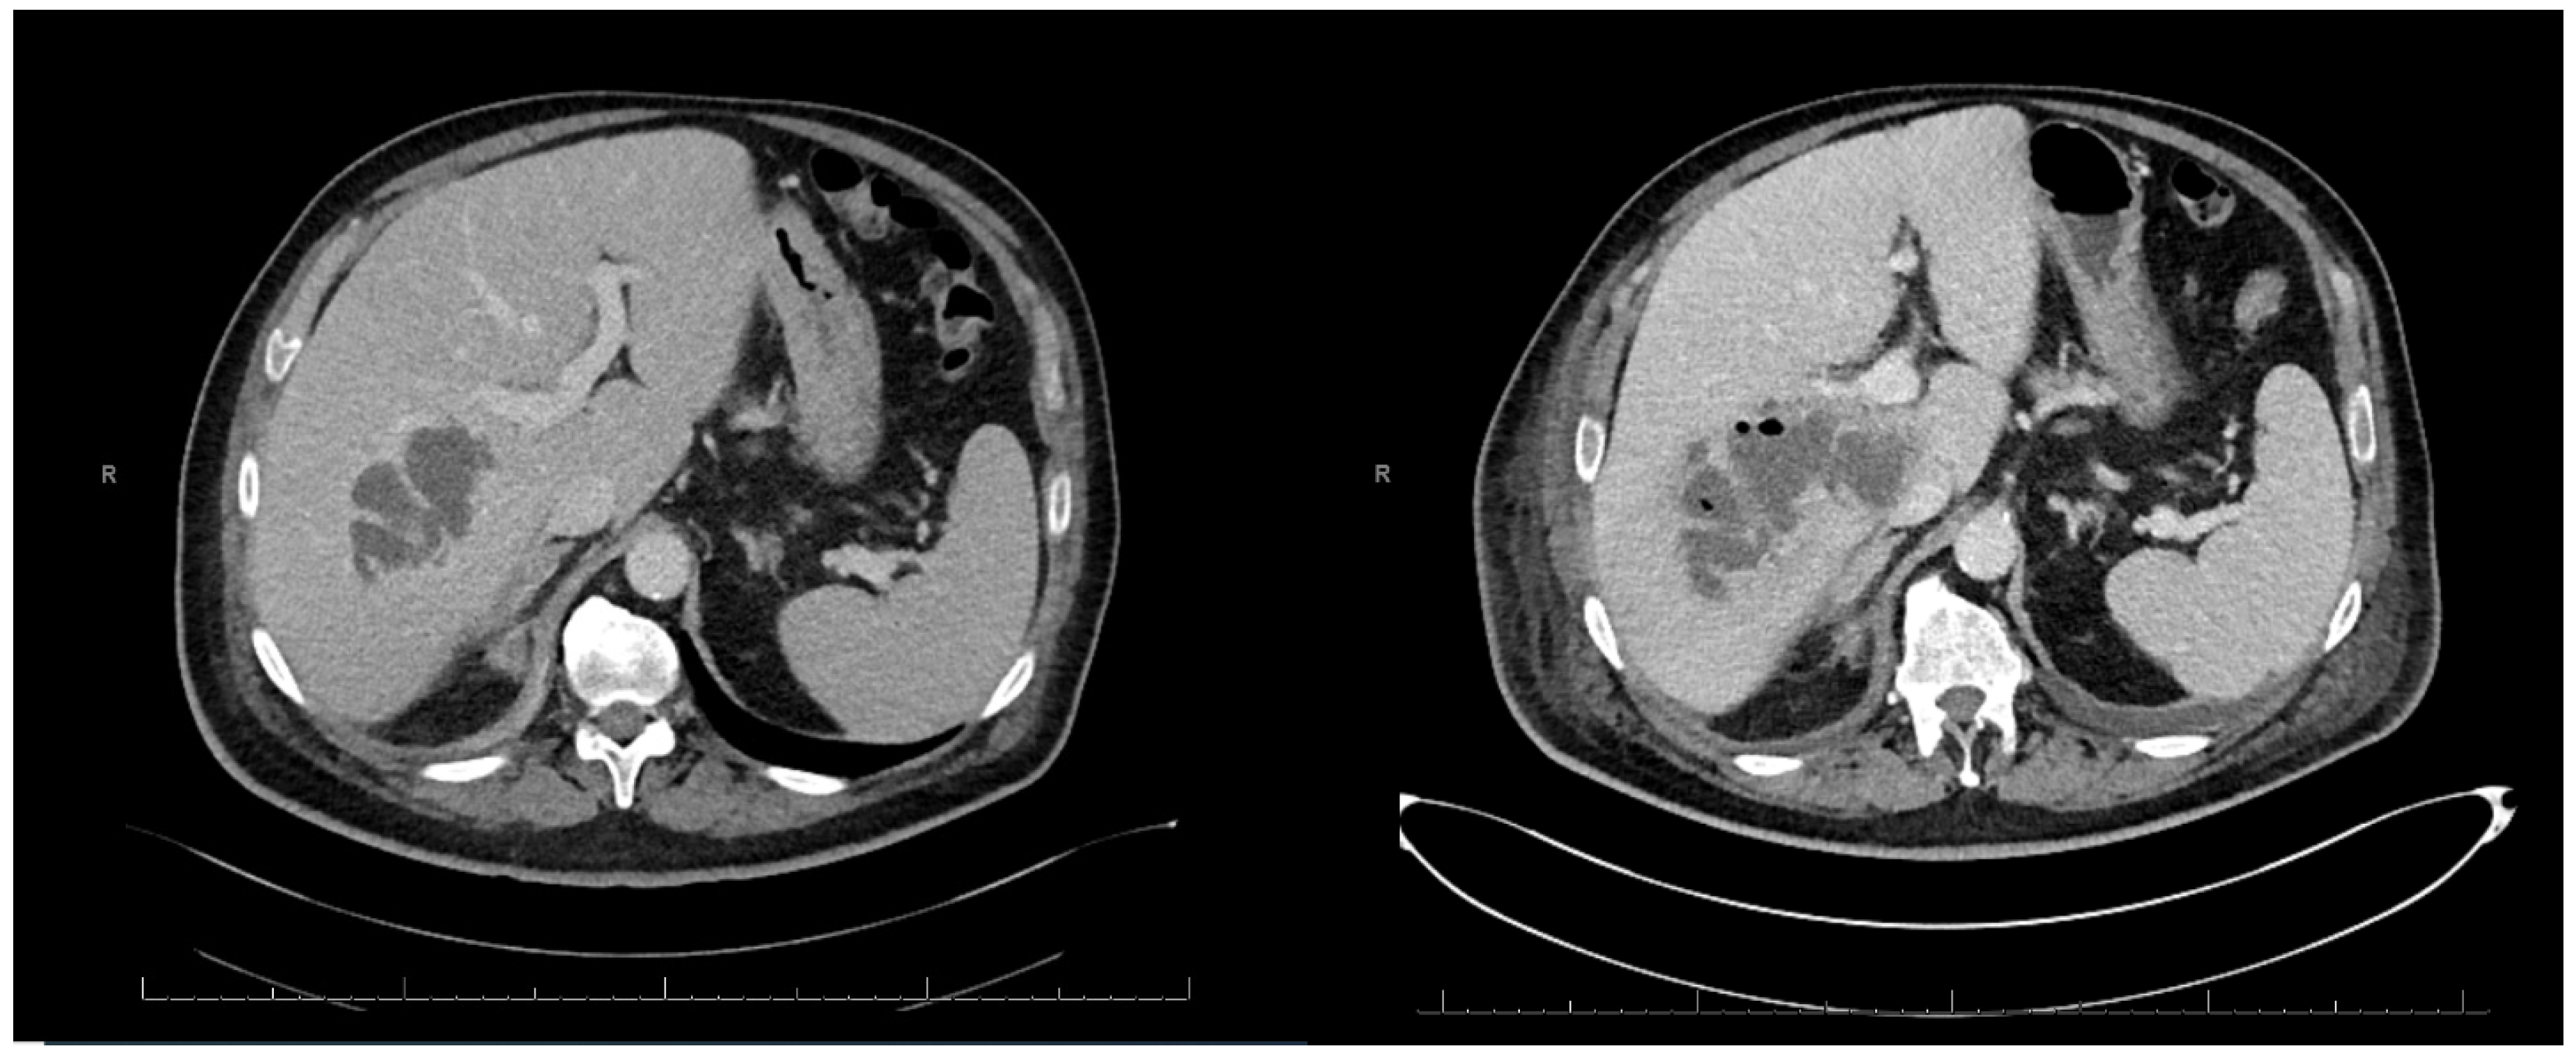

2. Case Report